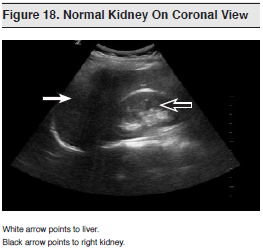

Ultrasound of the renal and urinary system is easily performed and is a core application of emergency ultrasound.1 It is fundamental to the evaluation of patients who present to the ED with undifferentiated flank or abdominal pain and is an integral component of the FAST examination. (See Figure 18) Although not typically a life-saving examination, renal and urinary tract ultrasound can expedite patient care and avoid exposing patients to unnecessary ionizing radiation. The scan focuses on identifying hydronephrosis, assessing for ureteral jets, and determining bladder volume. Possible additional findings on urinary tract ultrasound include renal cysts or masses and bladder masses as well as abdominal aortic aneurysms, which often present similarly.